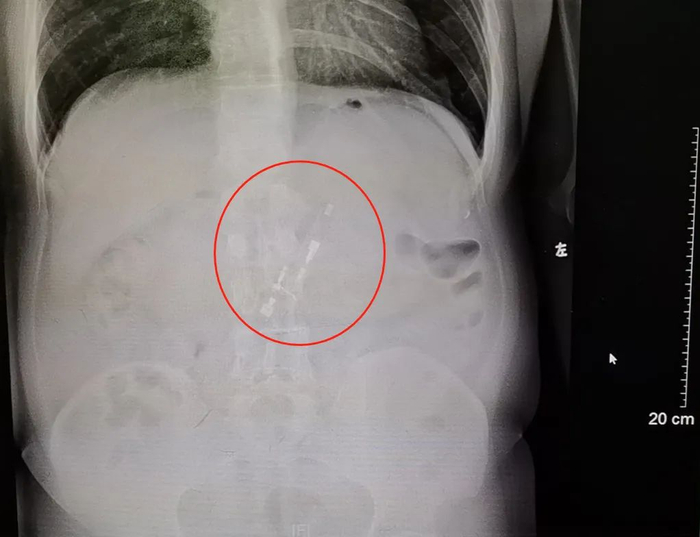

经过相关检查,陈叔的X光片显示,他的胃里有个白色条形物质——正是他几天前吞下的打火机。他这才紧张起来,连忙到消化内镜中心去做下一步的异物取出术。

X光片显示,胃里有个白色条形物质。通讯员供图

胃里的异物可能正是几天前吞下的打火机。通讯员供图